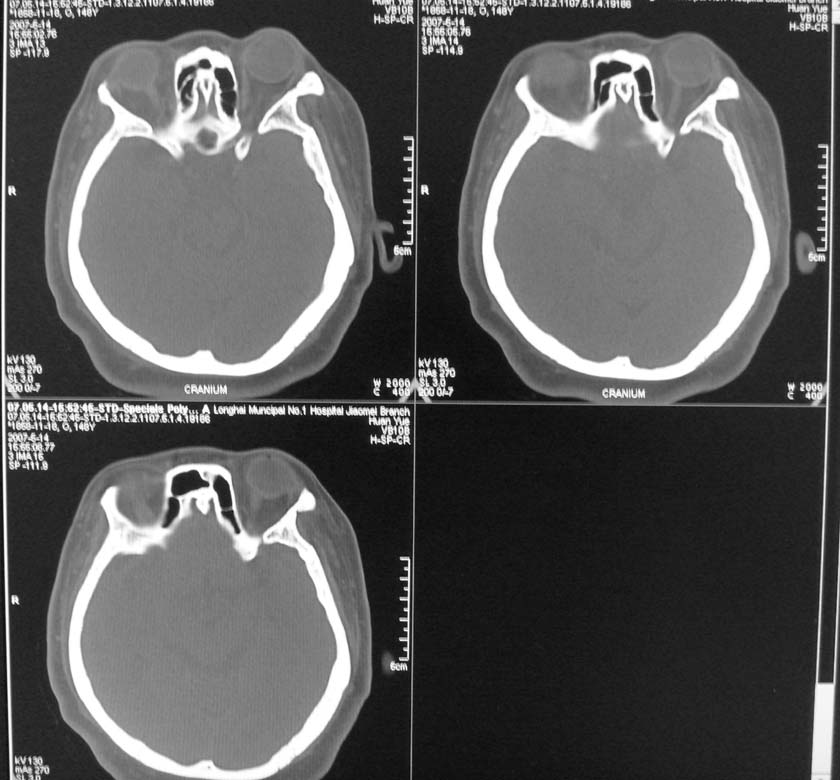

以下是引用天南地北在2007-5-15 23:30:00的发言:[br]看不出来什么[br]建议冠面增强扫描,或mri检查

以下是引用郭凯在2007-5-16 0:17:00的发言:[br]看不到,如果临床支持的话还是做mri看一下吧,对垂体微腺瘤比较敏感.[br]ct上看不到不能乱报.

以下是引用jiangjing在2007-5-16 11:06:00的发言:[br]看不出来什么[br]建议冠面增强扫描,或mri检查